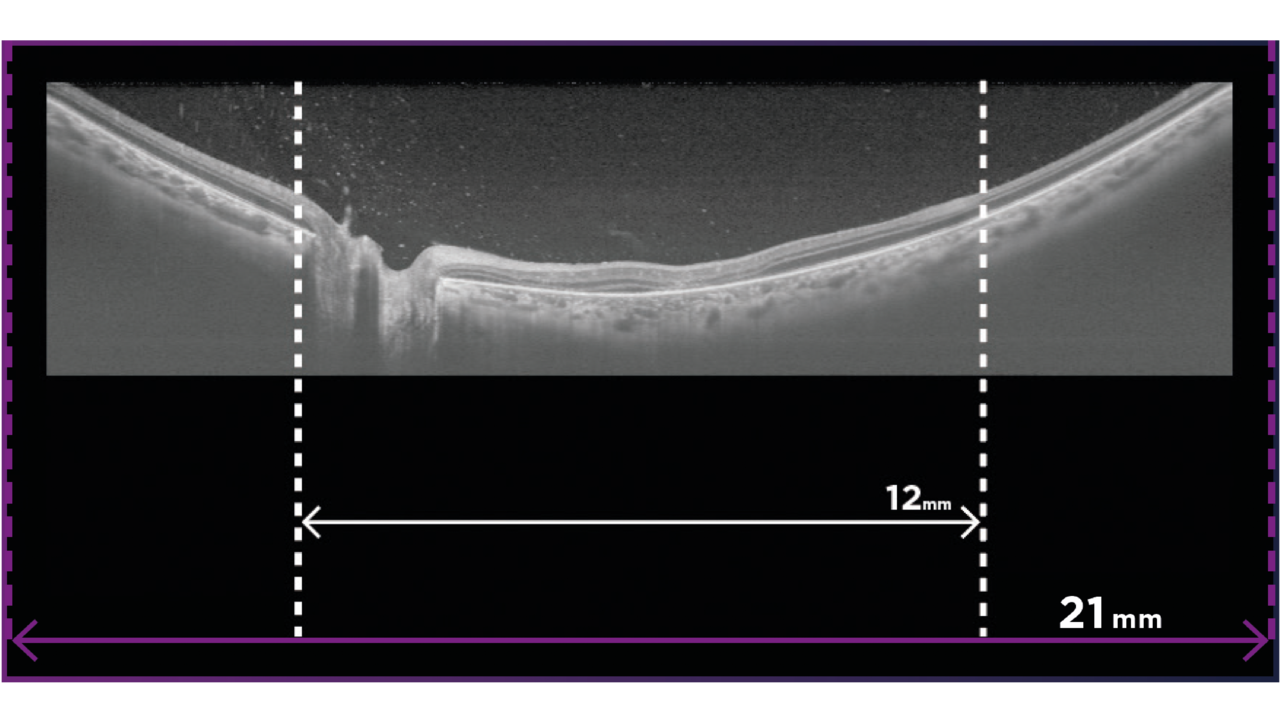

YENİ: Geniş Alan OCT ve OCT-A

İsteğe bağlı Geniş Alan ek lens, 21 mm uzunluğa kadar taramaların yakalanmasını sağlar. OCT ve OCT-A görselleştirme ile daha fazla klinik bilgi edinin. Geniş Alan görüntüleme, çok çeşitli durumlarda değerlidir.